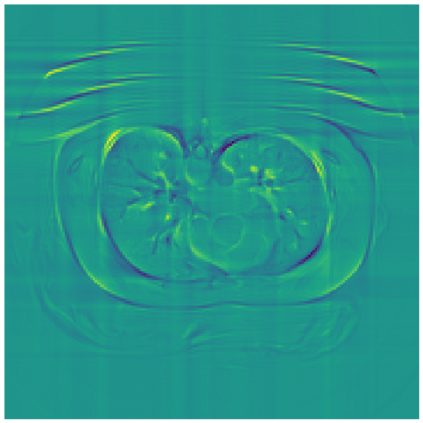

Sparse-view computed tomography (CT) -- using a small number of projections for tomographic reconstruction -- enables much lower radiation dose to patients and accelerated data acquisition. The reconstructed images, however, suffer from strong artifacts, greatly limiting their diagnostic value. Current trends for sparse-view CT turn to the raw data for better information recovery. The resultant dual-domain methods, nonetheless, suffer from secondary artifacts, especially in ultra-sparse view scenarios, and their generalization to other scanners/protocols is greatly limited. A crucial question arises: have the image post-processing methods reached the limit? Our answer is not yet. In this paper, we stick to image post-processing methods due to great flexibility and propose global representation (GloRe) distillation framework for sparse-view CT, termed GloReDi. First, we propose to learn GloRe with Fourier convolution, so each element in GloRe has an image-wide receptive field. Second, unlike methods that only use the full-view images for supervision, we propose to distill GloRe from intermediate-view reconstructed images that are readily available but not explored in previous literature. The success of GloRe distillation is attributed to two key components: representation directional distillation to align the GloRe directions, and band-pass-specific contrastive distillation to gain clinically important details. Extensive experiments demonstrate the superiority of the proposed GloReDi over the state-of-the-art methods, including dual-domain ones. The source code is available at https://github.com/longzilicart/GloReDi.